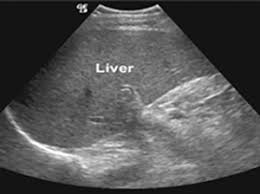

초음파 검사: 간암의 조기 발견을 위한 첫 번째 단계로 종종 사용됩니다. 이 검사는 비침습적이며, 간의 이상을 찾는 데 도움이 될 수 있습니다.